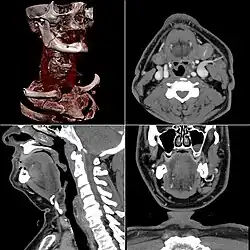

Images generated from computed tomography, including a 3D rendered image at upper left

Computed tomography or CT scan (previously known as CAT scan, the "A" standing for "axial") uses ionizing radiation (x-ray radiation) in conjunction with a computer to create images of both soft and hard tissues. These images look as though the patient was sliced like bread (thus, "tomography" – "tomo" means "slice"). Though CT uses a higher amount of ionizing x-radiation than diagnostic x-rays (both utilising X-ray radiation), with advances in technology, levels of CT radiation dose and scan times have reduced.[9] CT exams are generally short, most lasting only as long as a breath-hold, Contrast agents are also often used, depending on the tissues needing to be seen. Radiographers perform these examinations, sometimes in conjunction with a radiologist (for instance, when a radiologist performs a CT-guided biopsy).